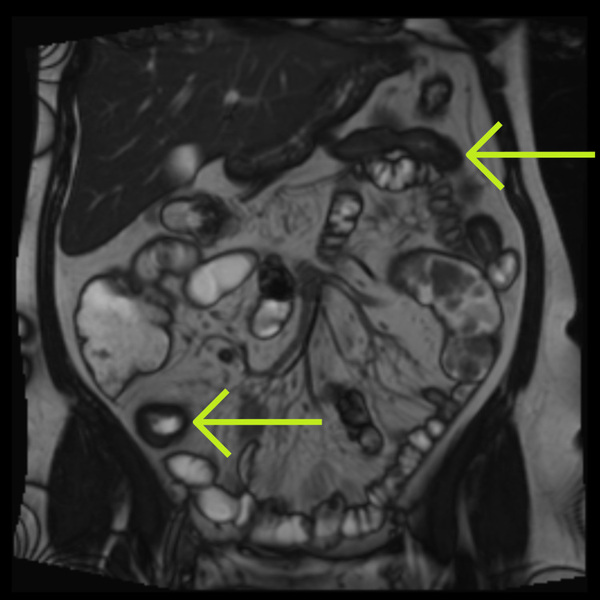

Small bowel strictures in Crohn's disease: a quantitative investigation of intestinal motility using MR enterography

A static stricture and pre-stricture dilation with reduced motility

A static stricture but some activity pre-dilation

A lively stricture with some contractions in the stricture and vigorous peristalsis upstream